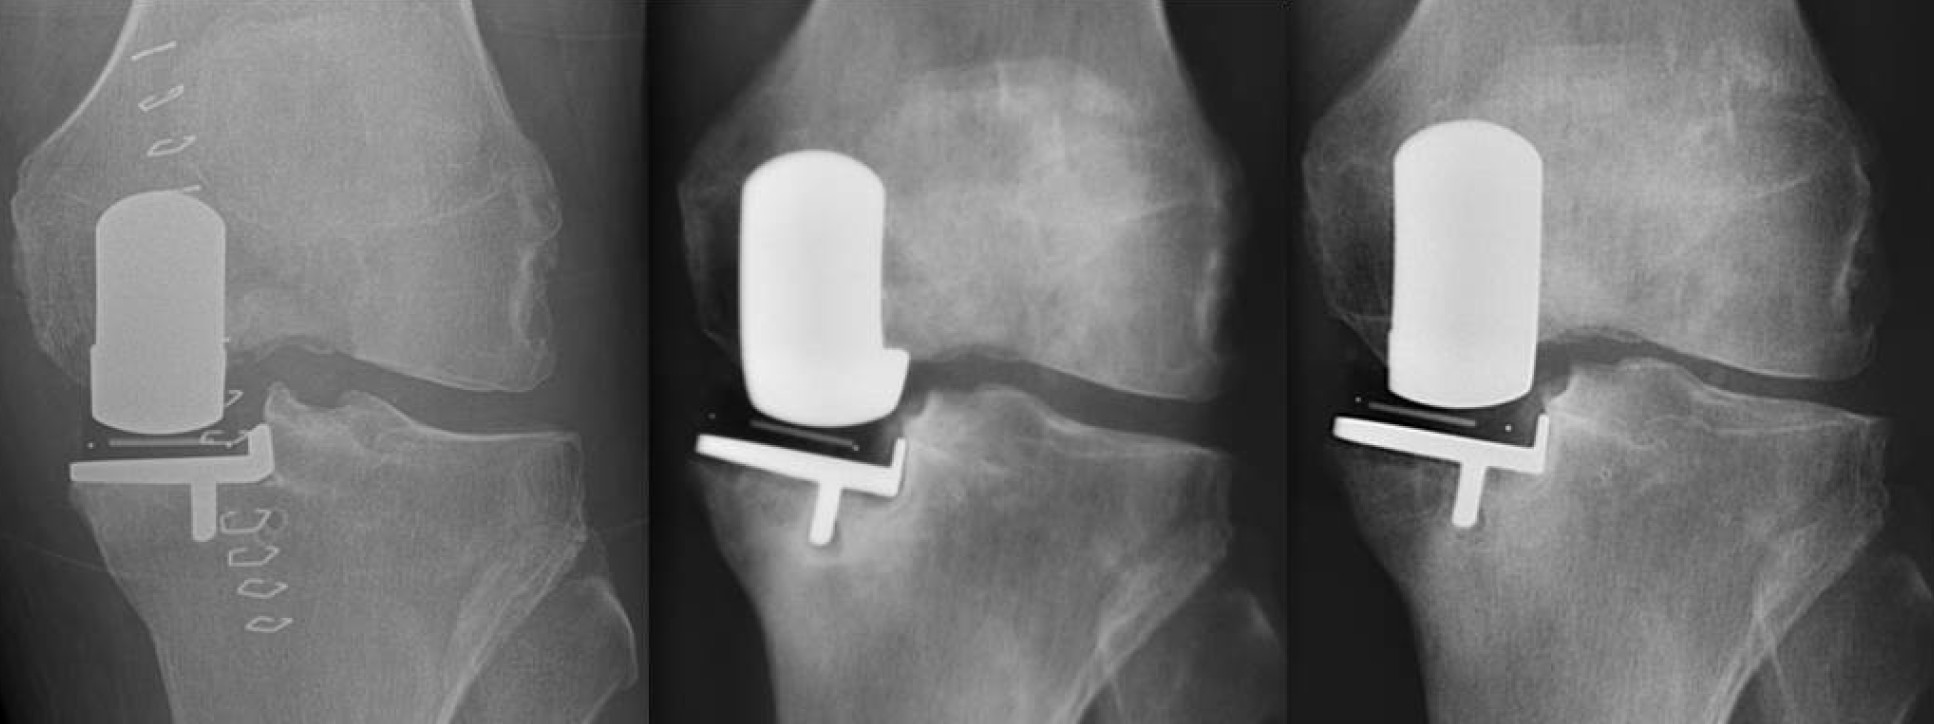

Novel techniques and designs in knee replacement

This work, in collaboration with Jonathan Jeffers at the Department of Mechanical Engineering, aims to improve the outcomes of knee replacement surgery by improving materials, design and implantation of partial and total knee replacements.